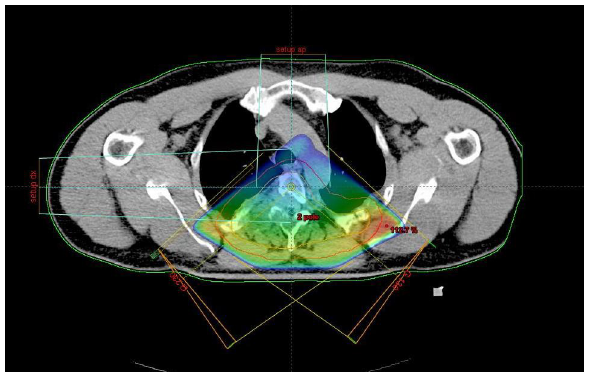

Extrakraniální SBRT/SRS

- U solitárních metastáz či oligometastáz

- Když není vhodná chirurgická metastazektomie

- Nevýhoda(??): chybí histologie z resekátu

- Nutné vybavení pracoviště a zkušenost